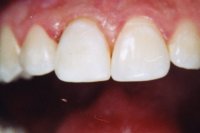

Ein 9-jähriges Mädchen kam eine Stunde nach einem Sturz, bei welchem es den linken oberen mittleren Schneidezahn komplett herausgeschlagen und den rechten massiv traumatisiert hatte (wackelte sehr stark), in unser Praxis (Röntgenbild Abb. 3). Der herausgeschlagene Zahn wurde sofort replantiert und beide mittleren Schneidezähne in die ursprüngliche Lage zurückversetzt und in dieser Situation mittels eines Drahtbogens an die Nachbarzähne fixiert (Röntgenbild Abb. 4).

Die verletzten Schneidezähne mussten beide wurzelbehandelt werden (Röntgenbild Abb. 5, siehe auch Kapitel Endodontie).

Einen Monat später haben wir beide Zähne intern gebleicht und dann die abgebrochenen Zähne wieder aufgebaut (Abb. 6 und 7).